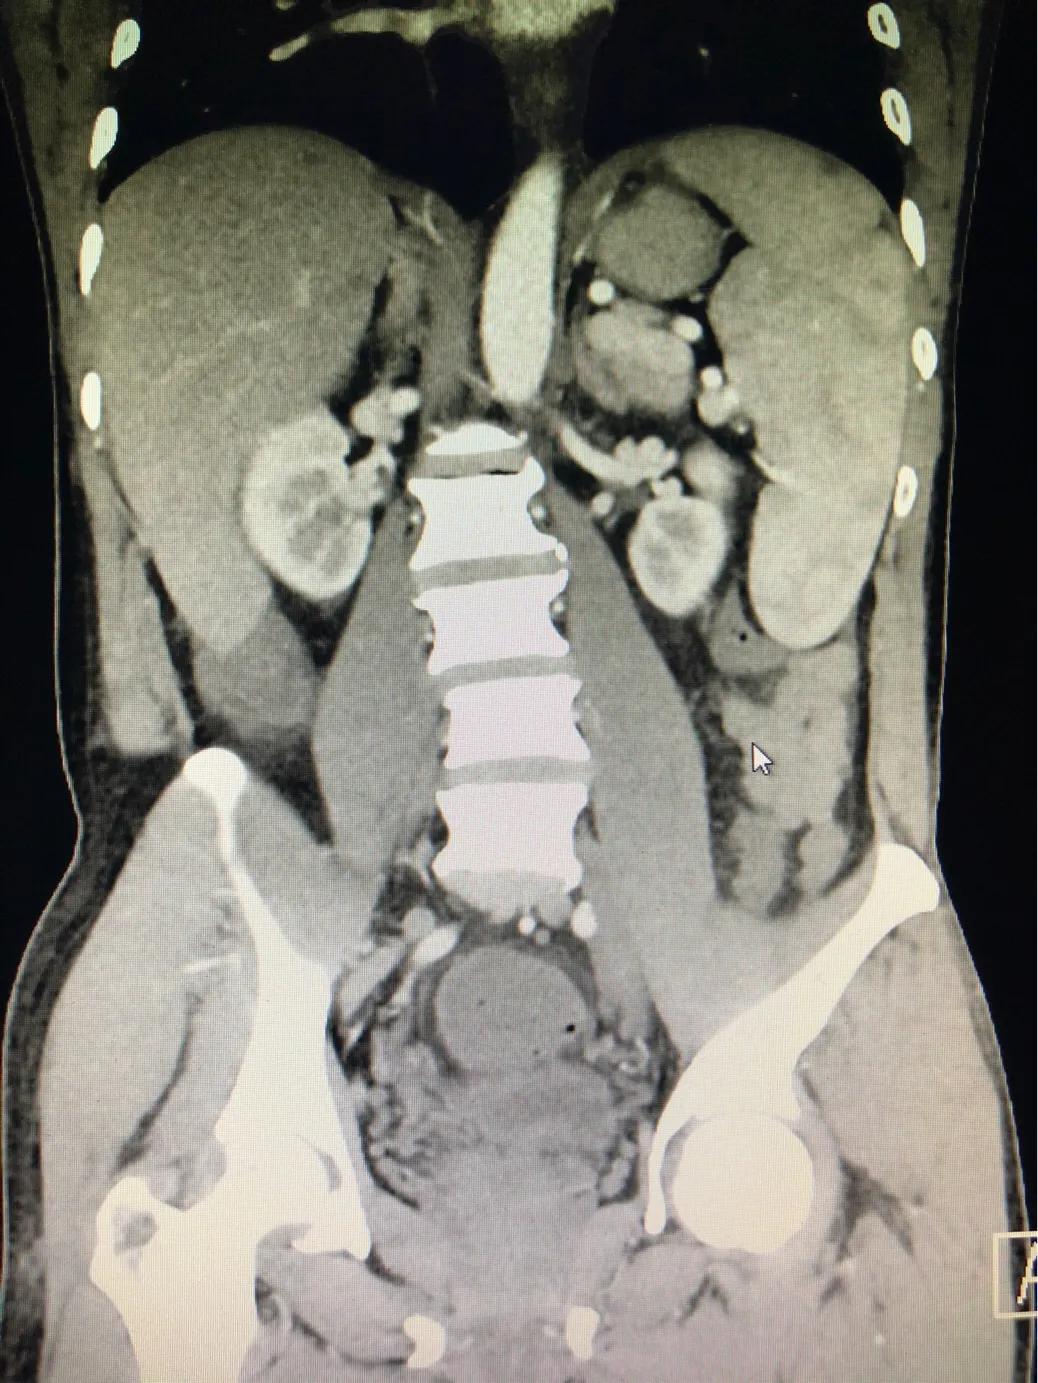

该图片提示脾脏增大